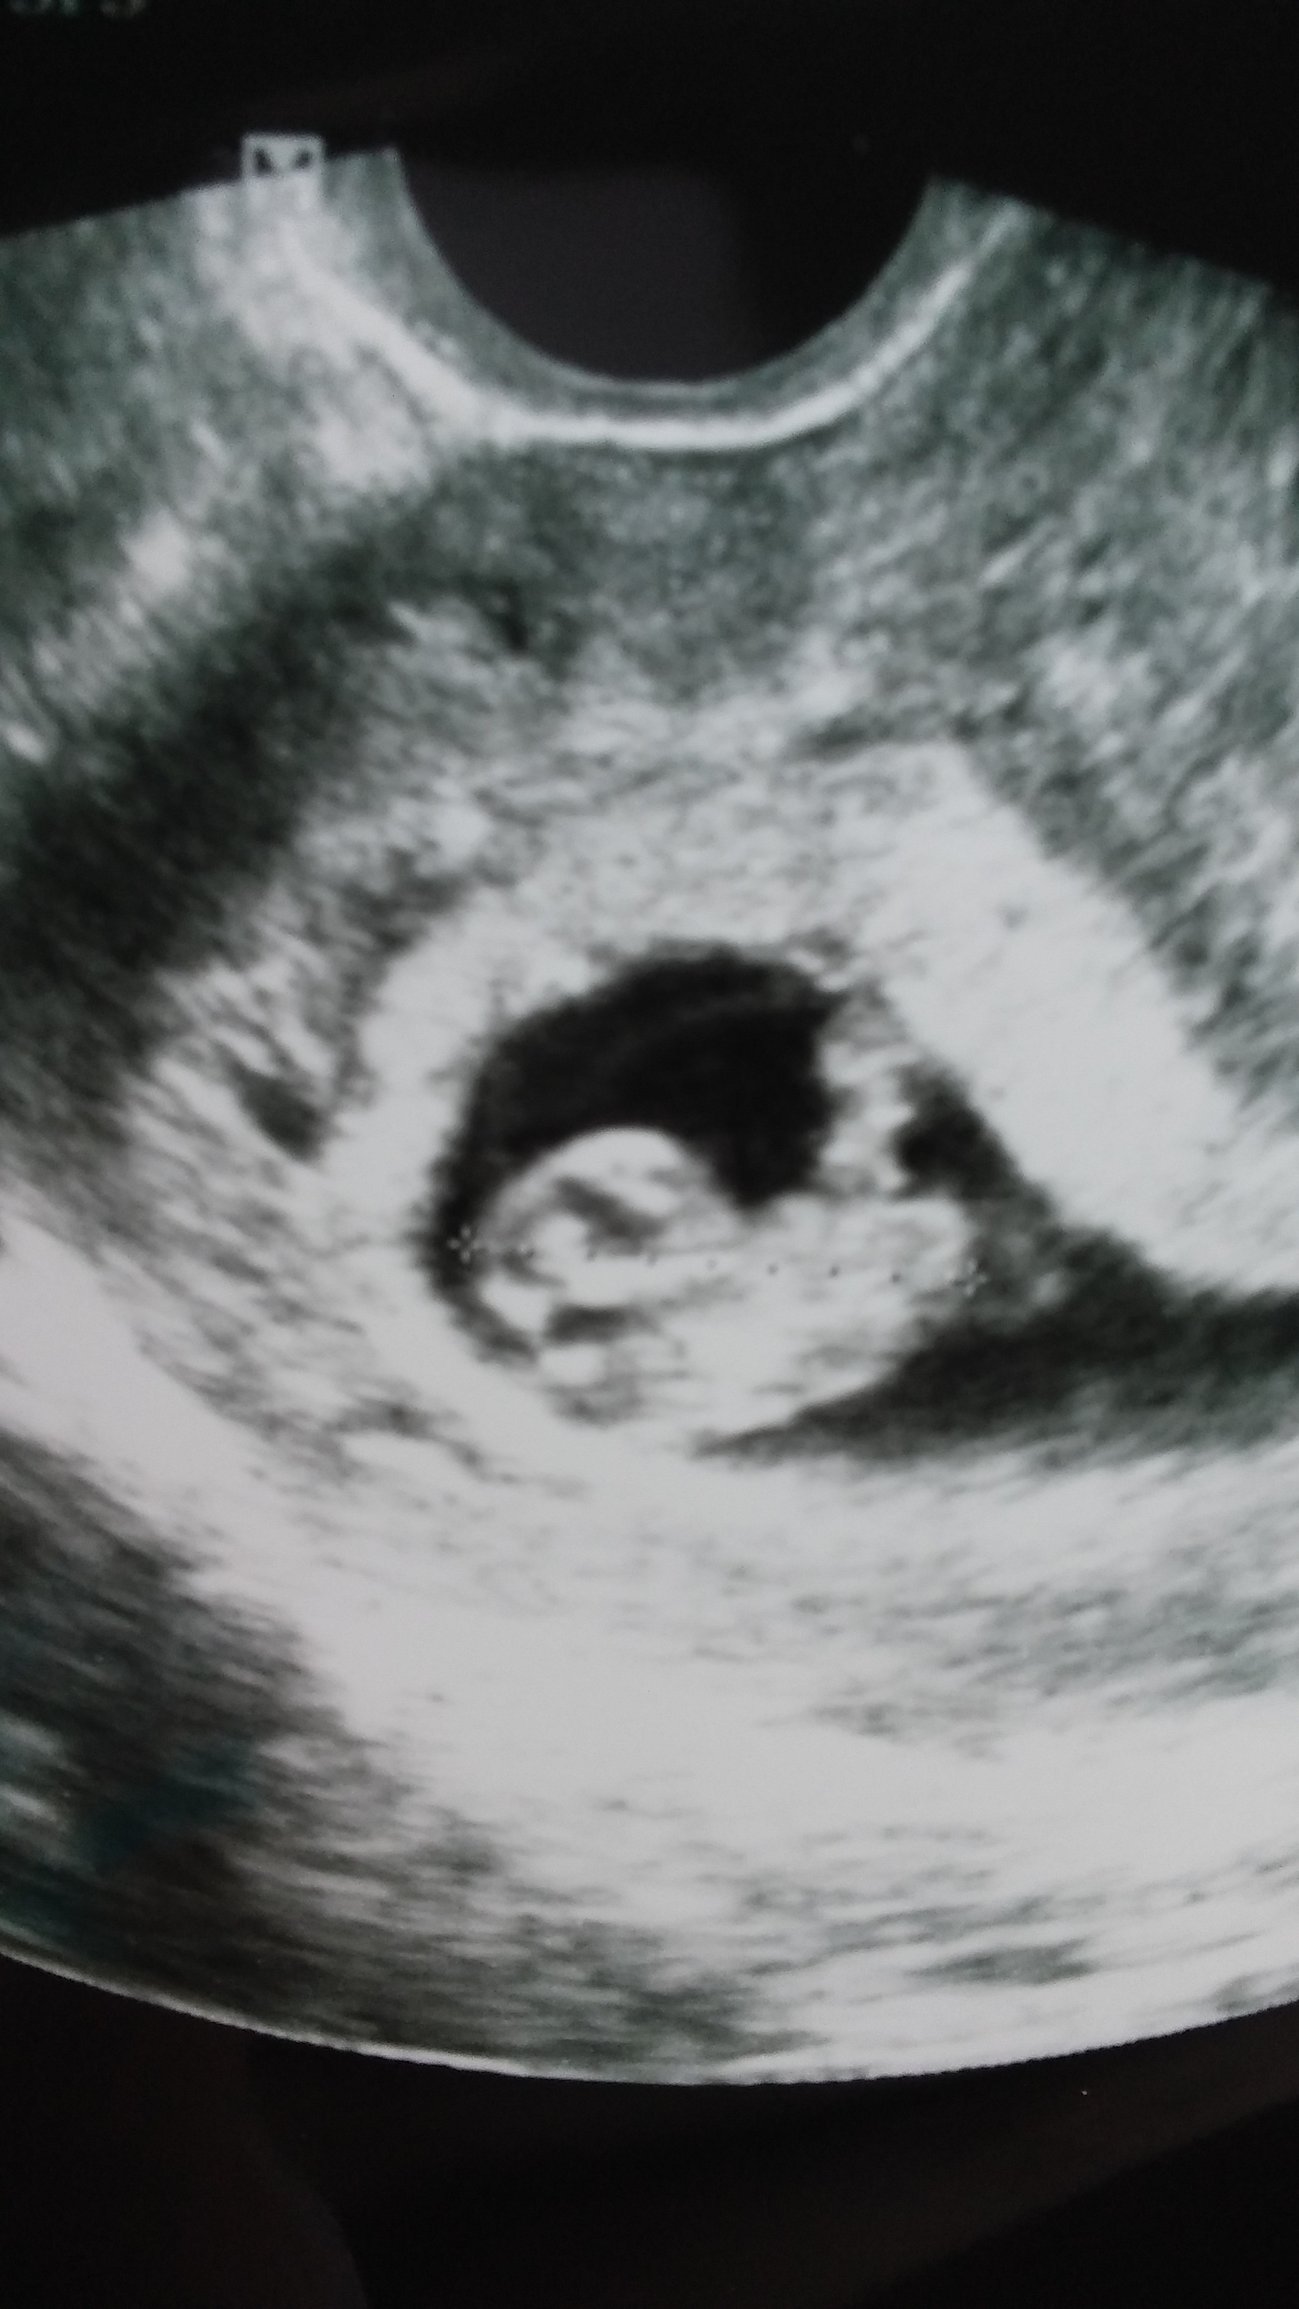

Went to the doctor's for an early ultrasound because I thought I was miscarrying. Turns out that's not quite the case! It's still early, 6 weeks 4 days, but 3 heartbeats!

Oh and it does not run in the family, and all natural conception!!